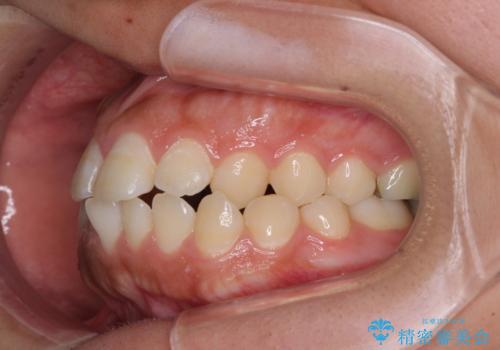

急速拡大とワイヤー抜歯矯正で唇を閉じやすく

- 口元の突出感を気にして来院された患者様です。

デコボコと口元の突出感が認められたため、上下左右の第1小臼歯4本を抜歯してのワイヤー矯正を行うこととしました。

上顎歯列の横幅が狭く、下顎大臼歯の歯軸が舌側に倒れていたため、急速拡大装置により上顎骨を側方に拡大し、咬み合わせを改善することとしました。

上顎歯列幅を拡大したことで、デコボコを容易に解消することができるようになったため、抜歯により得られたスペースを口元の突出感改善に利用することができました。